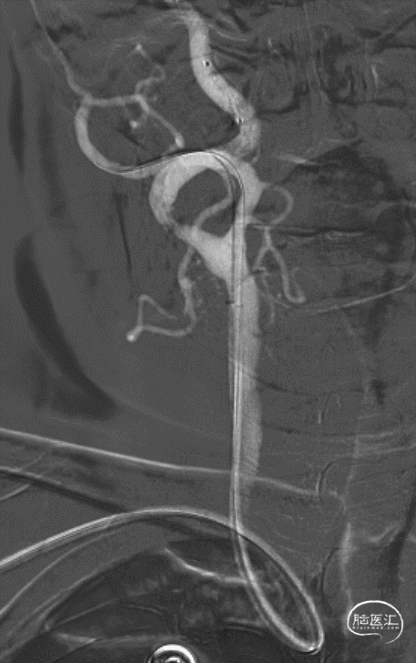

5.5F Simmons1.5通桥银蛇®Radial内管成袢超选右侧颈总动脉。

右侧颈总动脉正侧位造影。

正位造影

侧位造影

同轴导入7F 通桥银蛇®Radial外管。